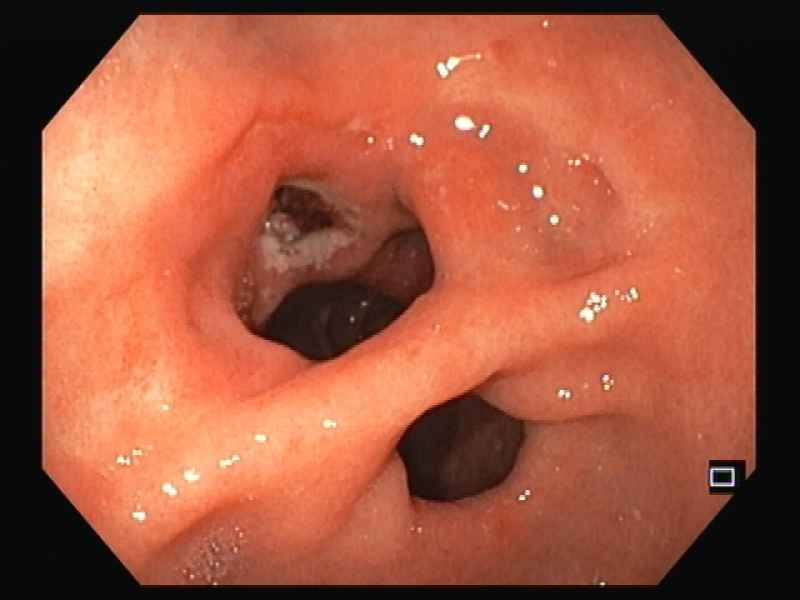

An exotic case of duodenal obstruction

Fotografia